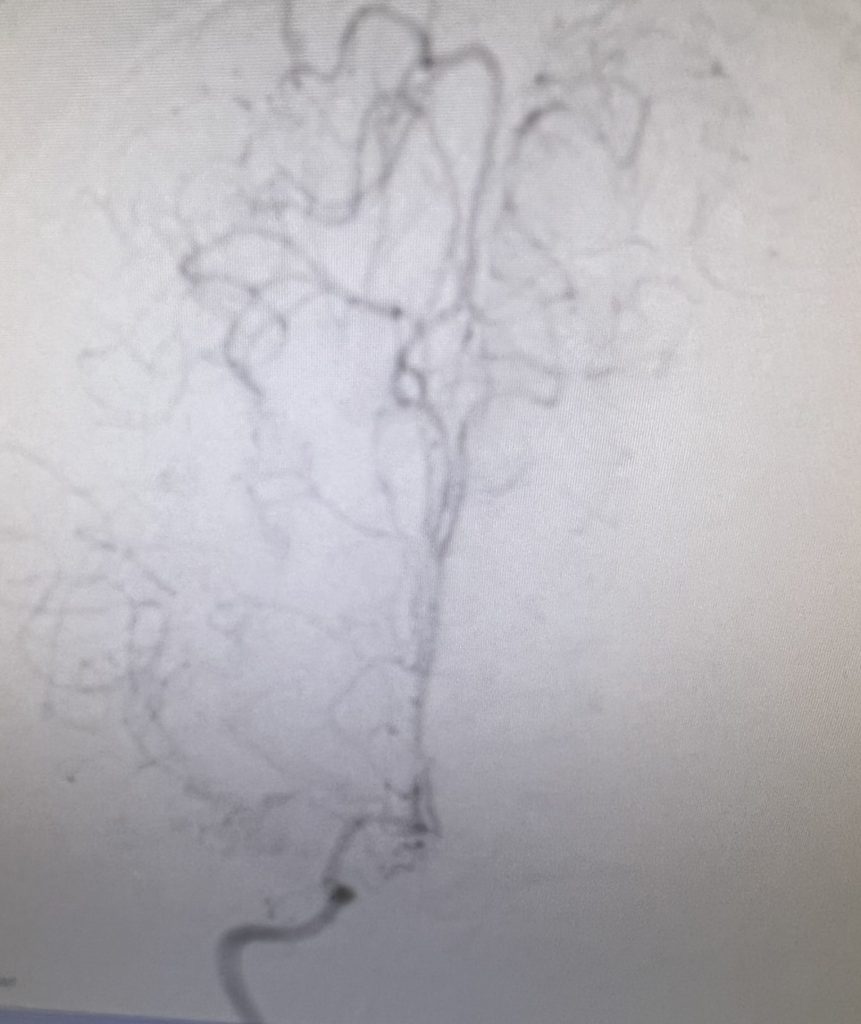

Noninvasive vascular imaging was sufficiently suggestive to warrant conventional digital subtraction angiography, performed by Dr. Brisman and confirming Moya-Moya syndrome (Figures 1). CT Perfusion (Figure 2) showed a decreased transit time of blood to the right hemisphere and the patient was recommended to undergo cerebral revascularization to avert stroke.

- Moya-Moya disease or syndrome (as in this case) is defined by bilateral stenosis and occlusions of the intracranial carotid and its main trunks, often with chronic engorgement and development of leptomeningeal collaterals at the base of the brain that resemble a “Moya-Moya” (Japanese word for puff of smoke) pattern on conventional angiography.